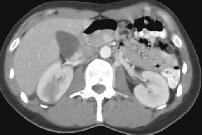

HELICAL CT FINDINGS: The CT was performed on AIC’s multi-slice helical CT (MSCT) scanner. Images with 5 mm collimation were obtained before, immediately following and 5-10 minutes after power injection of IV contrast. The region of the appendix was unremarkable. However, the right kidney and perinephric region were abnormal. Fig. 1 and Fig. 2 illustrate patchy and wedge-shaped low attenuation areas in the right kidney, and Fig. 3 shows stranding/infiltration of perinephric fat around the lower pole consistent with inflammatory changes (arrows).

DIAGNOSIS: The CT images are most compatible with acute pyelonephritis (APN) even without any laboratory results. Shortly after, results of blood work and urinalysis revealed leukocytosis and pyuria substantiating the CT diagnosis.